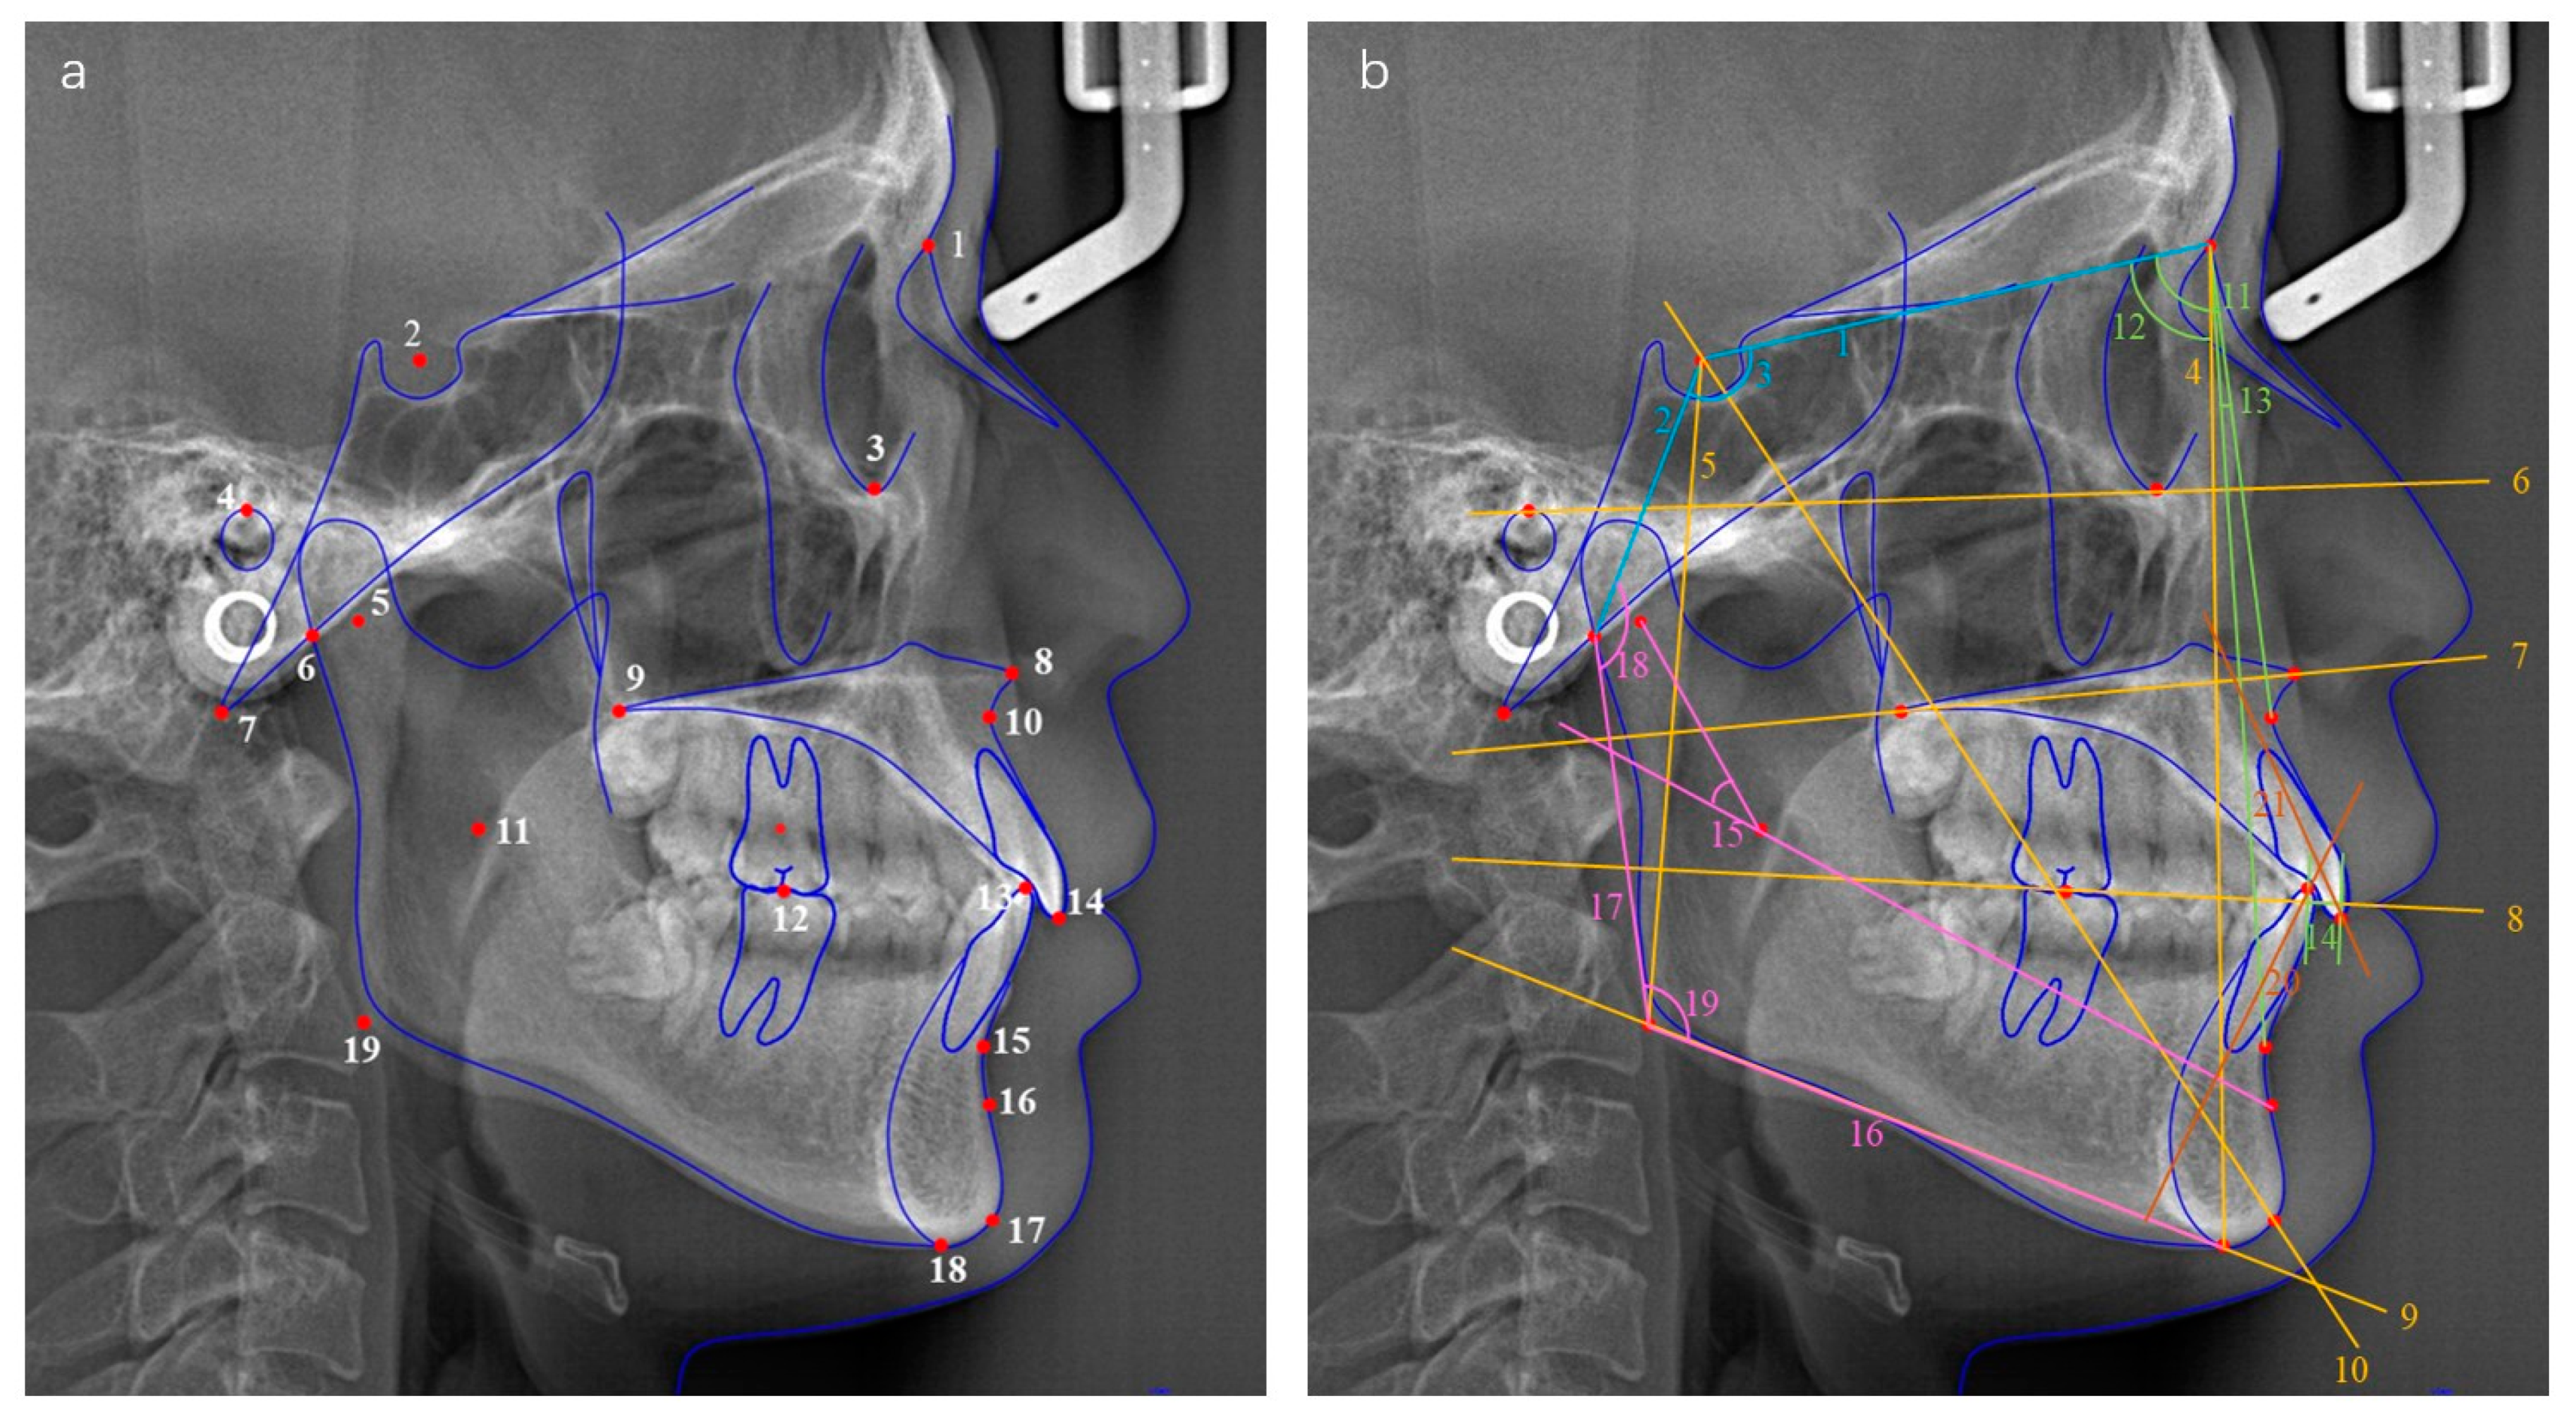

The cephalograms were shot by using an X-ray scanner (Morita, Osaka, Japan) with the standardized technique. Each patient was instructed to assume a natural head position and occlude in ICP without swallowing or chewing. Digital cephalograms were anonymized and then traced using Uceph software (version 961, Chengdu, China). The Frankfort horizontal plane (FH plane) was considered as the reference plane. A total of 24 measurements (Figure 2 and Table 1) were performed to evaluate the cranial base, vertical relationship, sagittal relationship, mandible position and morphology, and dental relationship, respectively. Sagittal skeletal pattern categorization was based on the ANB angle as follows: (1) skeletal class I (ANB < 1°), (2) skeletal class II (1° ≤ ANB ≤ 5°) and (3) skeletal class III (ANB > 5°). Two operators (C.Y. and X.X.) conducted the cephalometric tracing. The intra-observer and inter-observer reliability was verified before the study with a kappa coefficient >0.80 for all the measurement items.

Figure 2.

(a) Cephalometric landmarks used in the study. (1) N, nasion; (2) S, sella; (3) Or, orbitale; (4) P, porion; (5) Dc point; (6) Ar, articulare; (7) Ba, basion; (8) ANS, anterior nasal spine; (9) PNS, posterior nasal spine; (10) A point; (11) Xi point; (12) first molar occlusal point; (13) lower incisor occlusal point; (14) upper incisor occlusal point; (15) B point; (16) Pm point; (17) Gn, gnathion; (18) Me, menton; (19) Go, gonion. (b) Planes and angles used in the study. Cranial base (blue): (1) anterior cranial base length, S–N; (2) posterior cranial base length, S–Ar; (3) saddle angle. Vertical relationship (yellow): (4) anterior facial height, N–Me; (5) posterior facial height, S–Go; (6) Frankfort plane; (7) palatal plane; (8) occlusal plane; (9) mandibular plane; (10) Y-axis. Sagittal relationship (green): (11) SNA; (12) SNB; (13) ANB; (14) Wits. Mandible position and morphology (pink): (15) mandibular arc angle, Dc–Xi–Pm; (16) mandibular body length; (17) ramus height; (18) articular angle; (19) gonial angle. Dental relationship (orange): (20) LI axis; (21) UI axis.